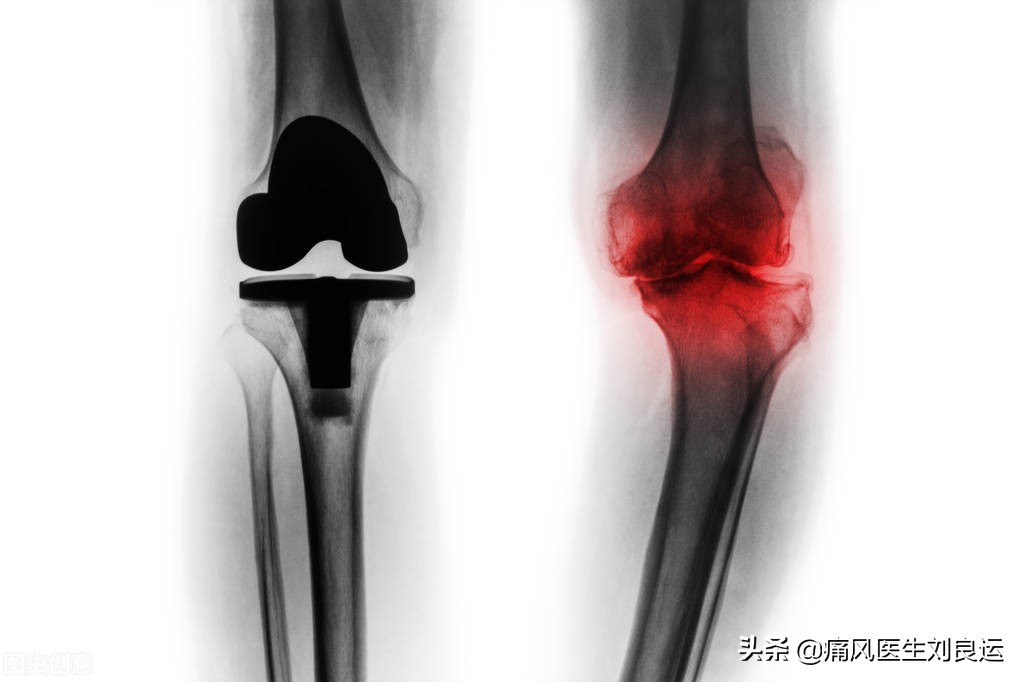

- 退行性关节炎与痛风发作的区别:退行性关节炎以老年人多见,一般临床是关节疼痛、功能障碍、关节肿大,此外还有晨僵、关节积液及畸形等,常发与颈椎、腰椎、膝关节、足跟骨和手指关节等。与痛风性关节炎不同的是,关节疼痛、麻木等症状会逐渐加重,而在手指、足趾等关节可以出现无症状的骨凸出物。

膝关节严重退行性关节炎病变